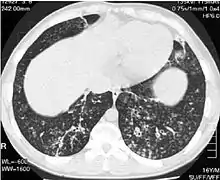

High-resolution computed tomography images of the lower chest in a 16-year-old boy with diffuse panbronchiolitis

High resolution computed tomography (HRCT) images of the lower chest in a 16-year-old boy initially diagnosed with DPB (left), and 8 weeks later (right) after a 6-week course of treatment with erythromycin. The bilateral bronchiectasis and prominent centri-lobular nodules with a "tree-in-bud" pattern shows noticeable improvement.